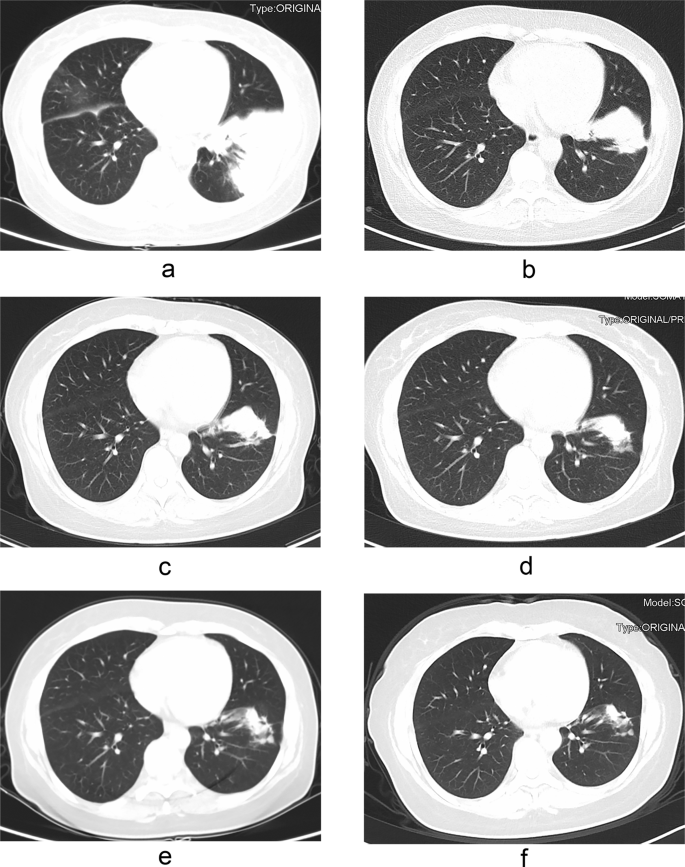

Radiologic outcomes after treatment

The available follow-up chest CT time in our hospital for immunocompromised patients was from 0.25 to 45 months, and 0.5 to 73 months for immunocompetent patients. After 3 months of treatment, 26 immunocompromised patients and 15 immunocompetent patients had follow-up chest CT scans in our hospital, 92.7% (38/41) of them have improved imaging findings. The time difference of CT imaging improvement in two groups was not statistically significant (P > 0.05) (see Table 6). The gradual radiologic improvement was found in the 43 patients who were treated with antifungal drugs even after their drug therapy was stopped. At the end of the follow-up period, complete radiologic remission could be found only in the six patients who underwent surgical resection. All the other patients had some residual abnormalities (such as high-density shadow, nodular shadow, pleural thickening, adhesion) and/or fibrotic scars. Figure 2 showed the changes of chest CT lesions during the follow-up of an immunocompromised patient with PC.

Pulmonary cryptococcosis in a 42-year-old woman with nephrotic syndrome and endometrial cancer after hysterectomy. CT imaging shows patchy consolidation in the left lower lobe of the lung (a). The lesion was significantly reduced after two months of treatment with fluconazole/voriconazole plus 5-fluorocytosine (b). The lesion continued to shrink after five months of treatment (c). The drug was discontinued after 13 months of treatment (d). The focus continued to shrink and there were still irregular soft tissue mass after 16 months (e) and 29 months (f) of drug withdrawal.